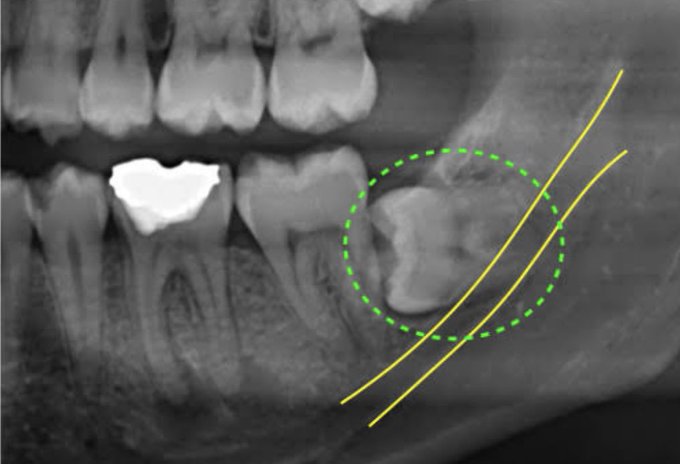

それはそれとして俺の親知らずの生え方まじ草だから見て

(ちな写真は似てるのネットから見つけた)